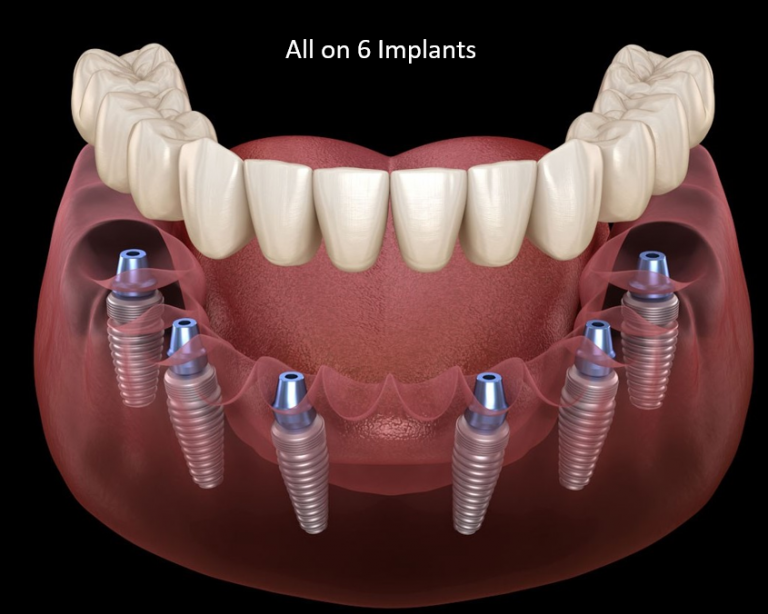

Dental Implants

Permanent tooth replacements anchored in the jawbone. Offers unmatched stability, aesthetics, and function—ideal for missing teeth restoration